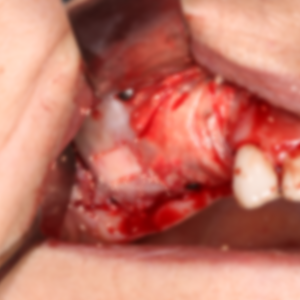

Sinus lift is usually performed under local anesthesia. After carefully lifting the sinus membrane, a bone graft is placed in this space. The graft can be made of synthetic materials or bone tissue taken from the patient's own body. During the healing process, new bone tissue forms in the area where the graft is placed, and this process usually takes 4-9 months. When sufficient bone volume is created, implants can be applied.

Under local anesthesia, the sinus membrane is carefully lifted and a bone graft is placed.